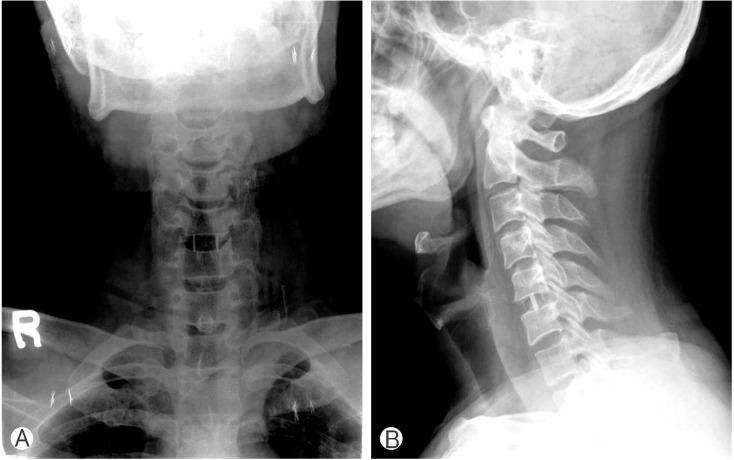

A total of 81 patients were enrolled for this study. Forty-five patients were included in a cervical plate group and the others were in stand-alone cage group. There was no statistical difference in pain score between the 2 groups. Segmental subsidence was observed in 7 patients (15.6%) in plate-assisted cervical fusion group, and 13 patients (36.1%) in stand-alone cage group. Segmental kyphosis was observed in 4 patients (8.9%) in plate-assisted cervical fusion group, and 10 patients (27.8%) in stand-alone cage group. There was statistical difference between the 2 groups.

本研究共纳入81例患者。45例患者纳入颈椎前路钢板组,其余患者纳入单纯椎间融合器组。两组间疼痛评分无统计学差异。颈椎前路钢板辅助融合组有7例患者(15.6%)出现节段下沉,单纯椎间融合器组有13例患者(36.1%)出现节段下沉。颈椎前路钢板辅助融合组有4例患者(8.9%)出现节段后凸畸形,单纯椎间融合器组有10例患者(27.8%)出现节段后凸畸形。两组间存在统计学差异。